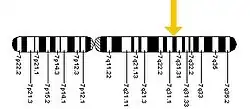

Se trata de una enfermedad autosómica recesiva. En su forma más común, una mutación de un aminoácido (falta una fenilalanina en la posición 508) conduce a un fallo del transporte celular y localización en la membrana celular de la proteína CFTR. Se han descrito más de mil ochocientas mutaciones,[31] siendo la mayoría de ellas pequeñas deleciones, aunque con diferentes efectos, como cambios en el marco de lectura, cambios de aminoácidos, terminación prematura de la proteína o alteraciones en el empalme (splicing) de ARNm.

El gen CFTR está localizado en el brazo largo del cromosoma 7, en la posición 7q31.2,[32] ocupando 180 000 pares de bases: más precisamente, desde el par 116 907 252 al 117 095 950 del cromosoma. Es un gen de gran tamaño, que posee 250 kb (kilobases) y que incluye veintisiete exones. Fue localizado y secuenciado por mapeo genético.

Este gen codifica la síntesis de un canal iónico de mil cuatrocientos ochenta aminoácidos, una proteína que transporta iones cloruro a través de las células epiteliales, y que controla la regulación de otros transportadores. En las personas con fibrosis quística, esta proteína está ausente o bien se encuentra en proporciones sensiblemente menores a las habituales.

En 1985, investigadores de Londres, Toronto y Salt Lake City trazaron el mapa del gen CFTR en el cromosoma 7q. Cuatro años más tarde, en 1989, Francis Collins, Lap-Chee Tsui y John R. Riordan descubrieron la primera mutación para la FQ, ΔF508, en ese cromosoma. Investigaciones posteriores a aquel hallazgo, identificaron más de mil mutaciones diferentes que dan origen a la enfermedad. Lap-Chee Tsui lideró el equipo de científicos del Hospital for Sick Children (un hospital escuela en convenio con la Universidad de Toronto) que descubrió el gen responsable de la FQ. Se trata del primer trastorno genético dilucidado estrictamente mediante el proceso de genética inversa. Debido a que las mutaciones del gen CFTR son generalmente pequeñas, las técnicas de la genética clásica o formal no fueron capaces de determinar con precisión el gen mutante.[79] Utilizando marcadores proteicos, los estudios de ligamiento genético lograron trazar un mapa de la mutación del cromosoma 7. Las técnicas de paseo y salto cromosómicos sirvieron entonces para identificar y secuenciar el gen.[80] Este gen fue uno de los primeros genes en ser localizado y secuenciado por mapeo genético, y algunos de los participantes en este proyecto, como Francis Collins estuvieron implicados más tarde en el Proyecto Genoma Humano